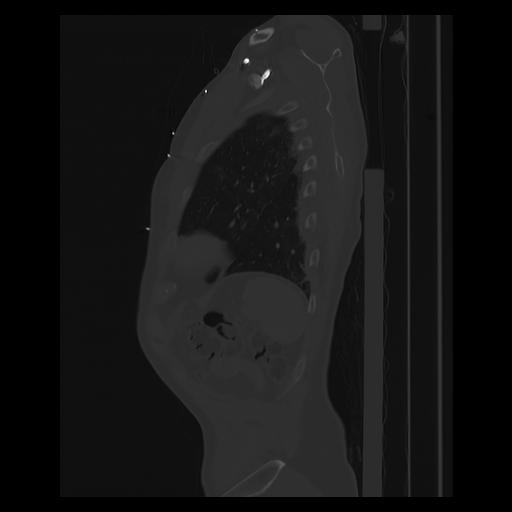

33 PULMON,CE,Sagittal,3.000,PULMON,Sagittal,